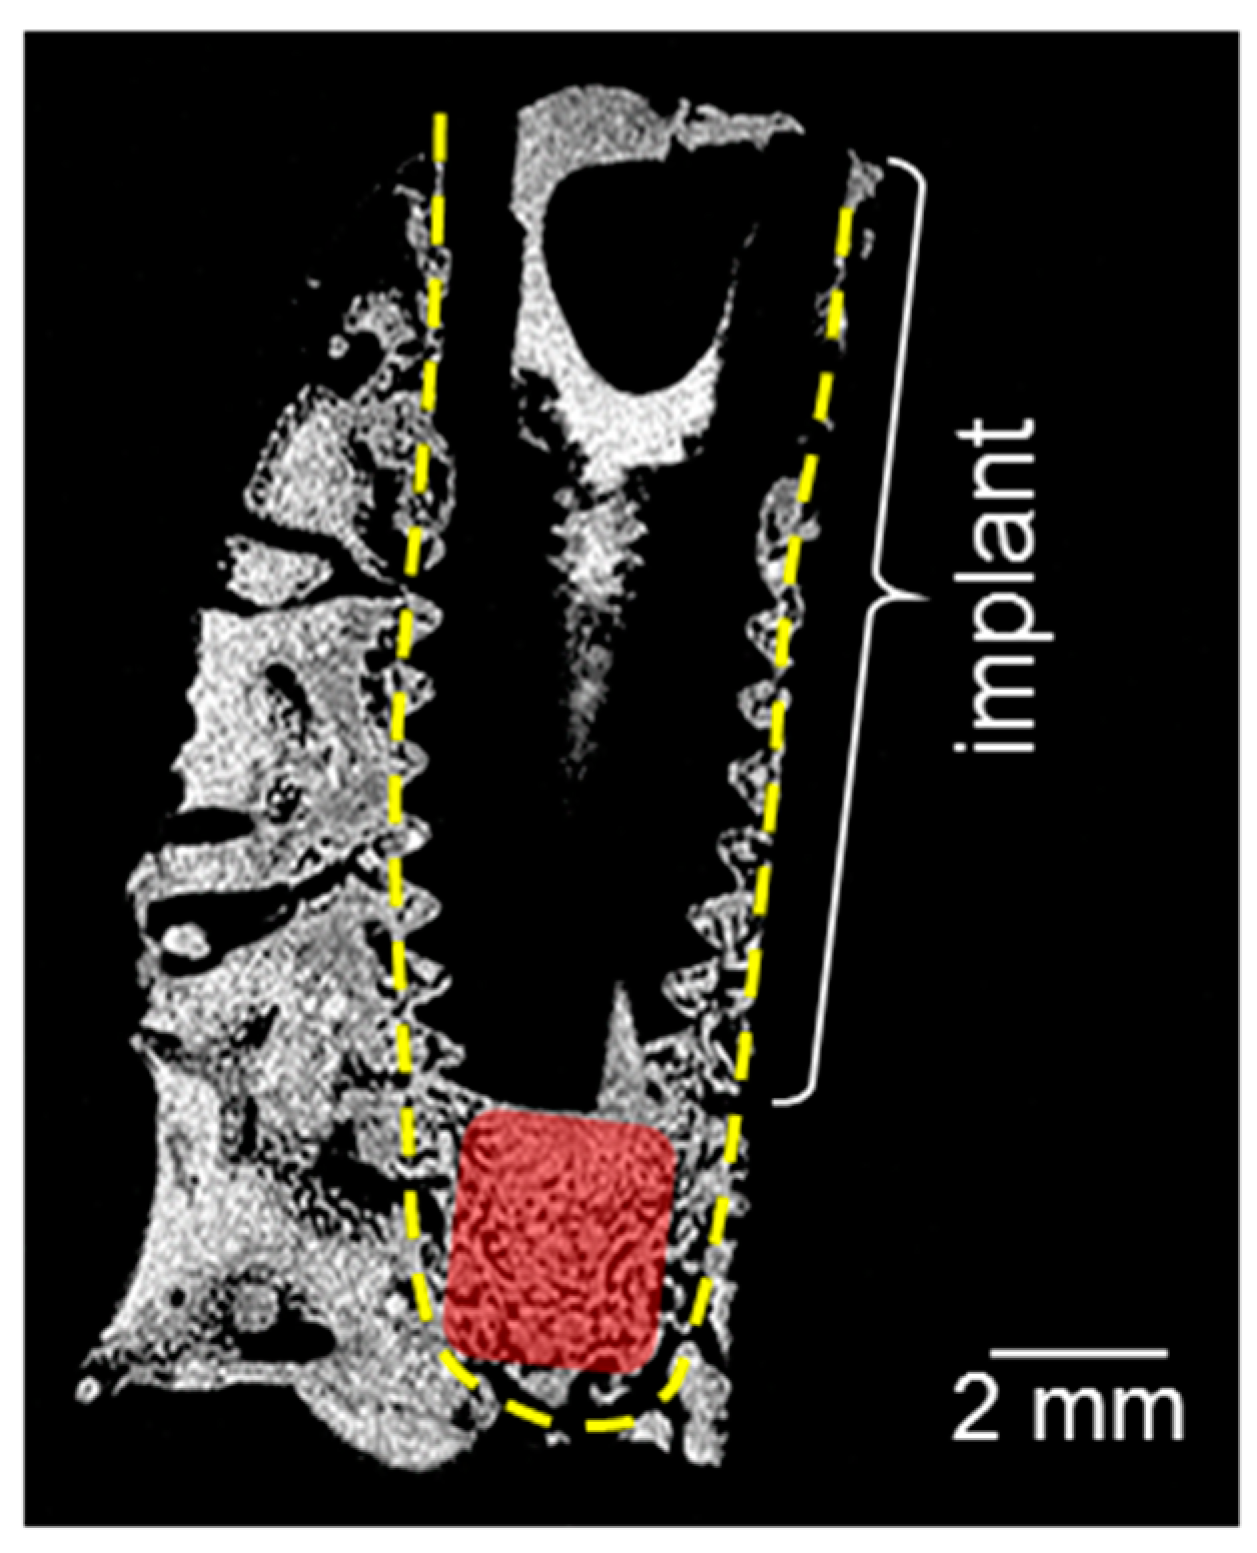

- Korn, P.; Elschner, C.; Schulz, M.C.; Range, U.; Mai, R.; Scheler, U. MRI and dental implantology: Two which do not exclude each other. Biomaterials 2015, 53, 634–645. [Google Scholar] [CrossRef] [PubMed]